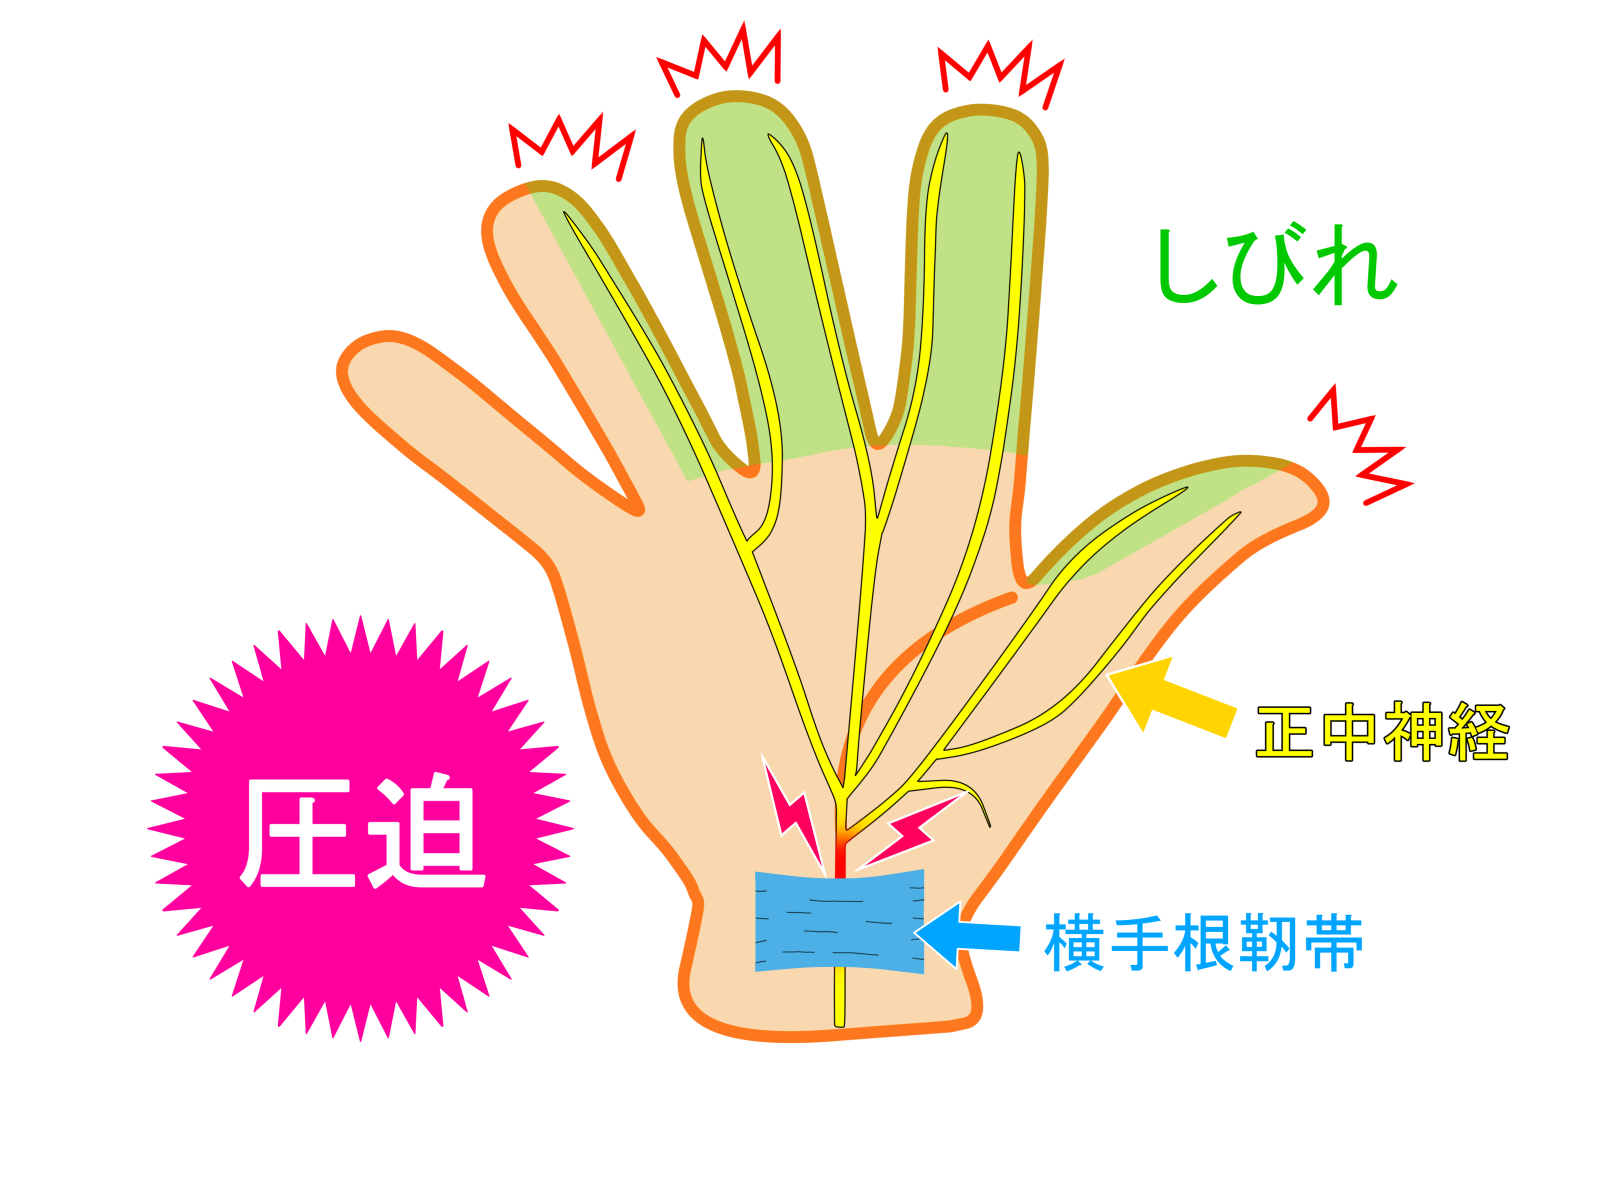

他の手や手首の繰り返しの動きと同様に、スマートフォンを長時間保持すると、正中神経への圧力が高まる可能性があります。

18歳以上の個人を対象とした2021年の研究では、1日2時間以上のスマートフォンの使用が手根管症候群の発症と関連していることが判明した。

1 日に 2 ~ 4 時間を携帯電話に費やすと、手根管症候群を発症する可能性が高まる可能性があります。スマートフォンを長時間頻繁に使用すると、手根管の症状が悪化する可能性があります。